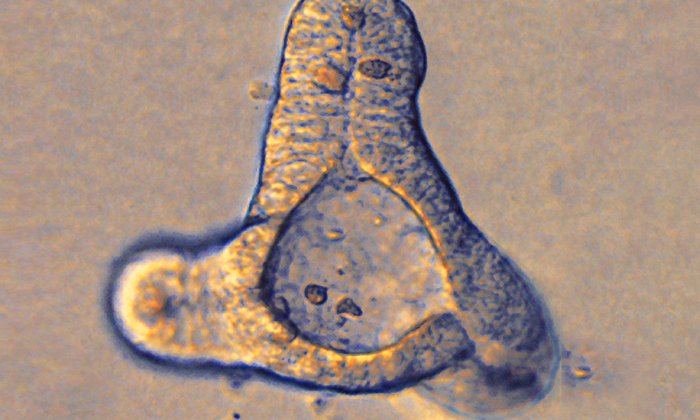

Gehirn-Organoide in einer Petrischale Andreas Heddergott / TUM

Mit solchen etwa 5 mm großen Organoiden lassen sich Erkrankungen des menschlichen Gehirns auf eine neue Art erforschen. Sie wachsen aus pluripotenten Stammzellen.